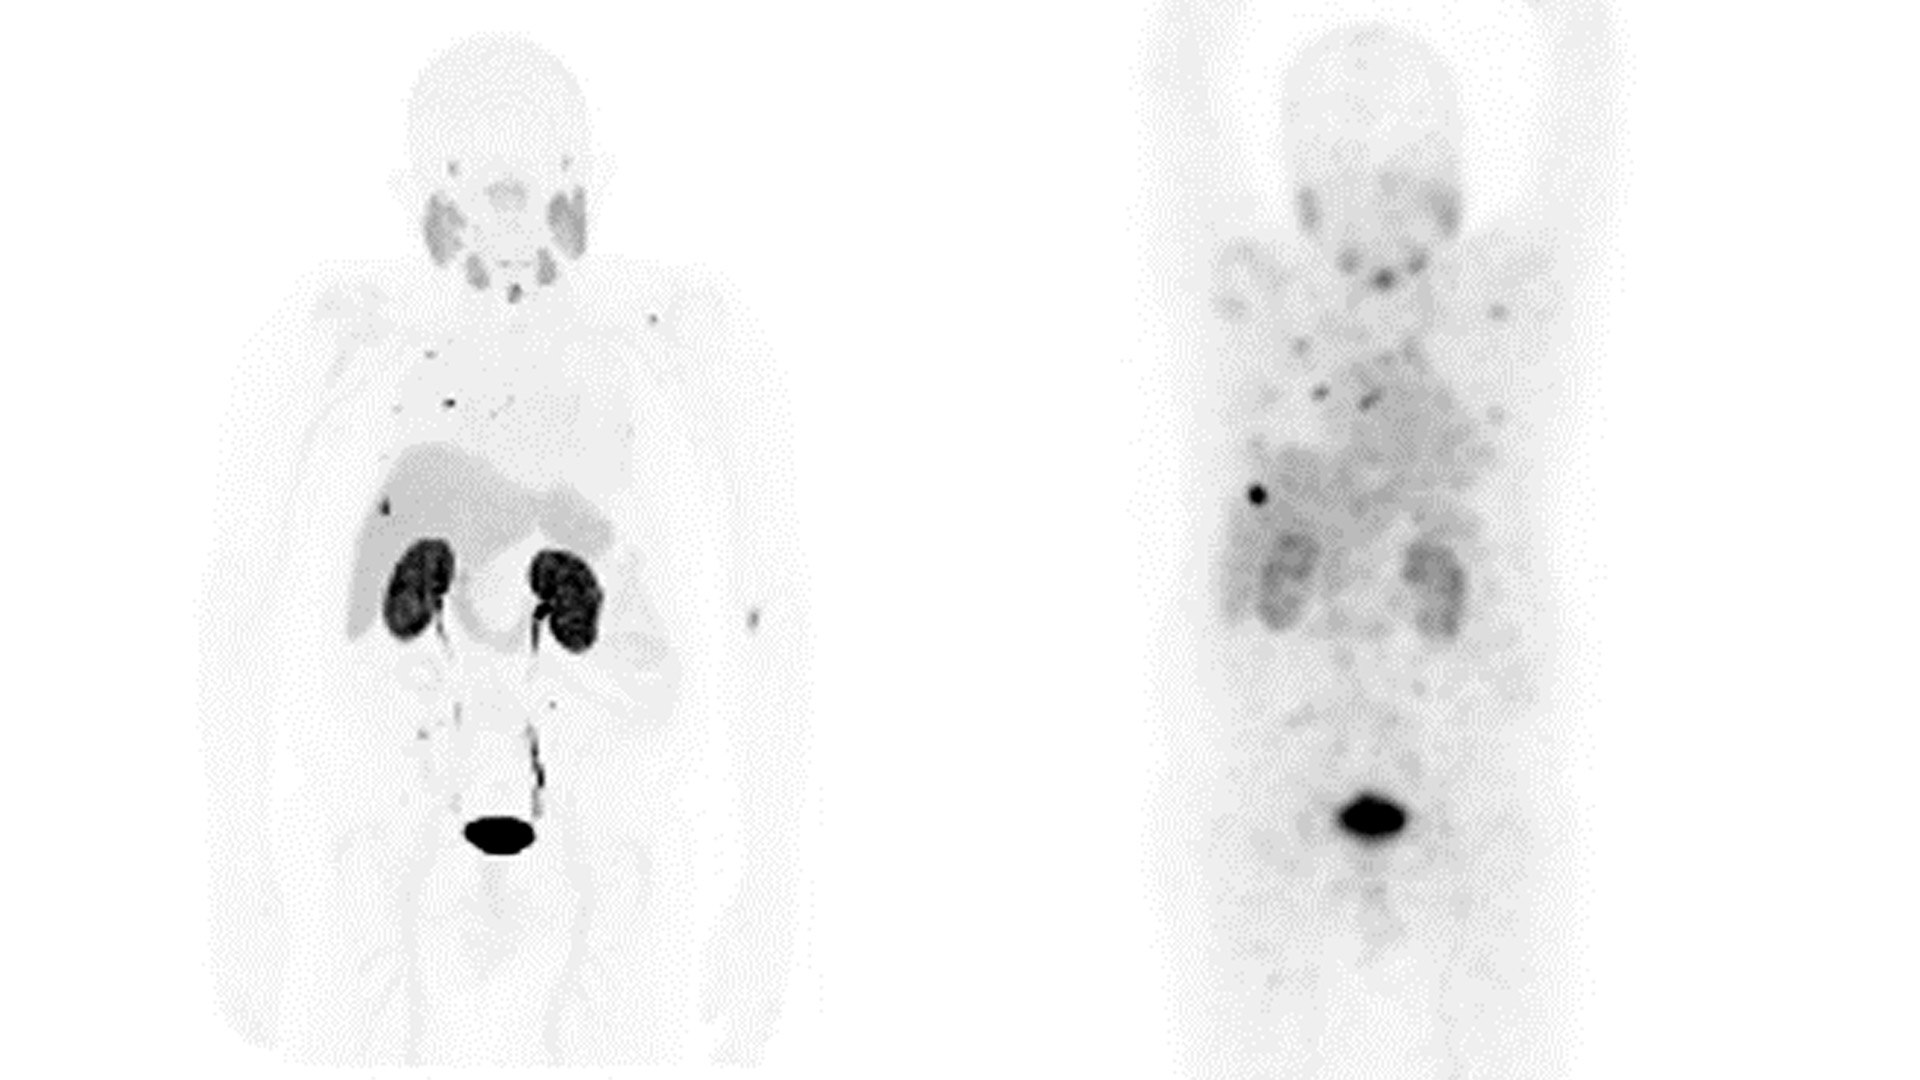

DIAGNOSIS

GE is pioneering the solutions that enable unparalleled sensitivity and diagnostic confidence.

Our dedicated portfolio of Theranostics-focused diagnostic imaging solutions was engineered specifically to meet clinicians’ needs—and those of their patients— today and in the future.